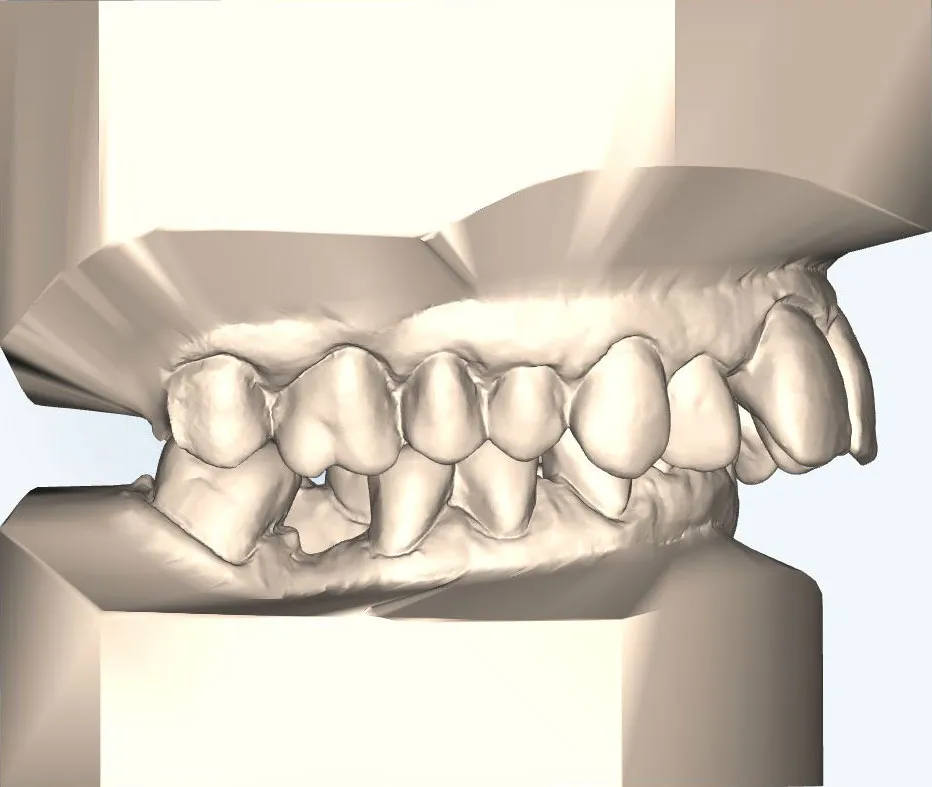

Für die kieferorthopädische Vor- und Nachbehandlung verwenden wir festsitzende Zahnspangen, die während und nach der Operation getragen werden müssen.

Für Patienten, die eine unauffällige Lösung bevorzugen, bieten wir die linguale Zahnspange an:

- Sie wird auf der Innenseite der Zähne befestigt und ist von außen nahezu unsichtbar.

- Die lingualen Zahnspange erziehlt durch ihre Individualisierung und ihrer lingualen Position eine sehr effiziente Kraftübertragung im Vergleich zur klassischen, festen Zahnspange – dabei ist sie zudem deutlich diskreter.

- Ideal für Beruf, Alltag und besondere Anlässe.